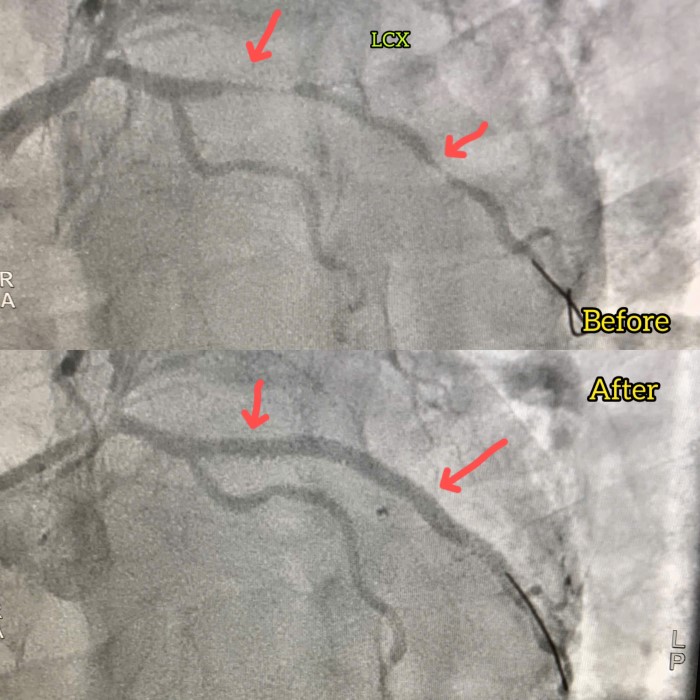

Tương tự, bệnh nhân V.B.T (59 tuổi, trú tại TP Đà Nẵng), bị tăng huyết áp, đái tháo đường, từng bị mạch mũ liên thất cách đây 12 năm và đã được phẫu thuật. Lần này bệnh nhân đau ngực nhiều nên vào viện. Sau khi tiến hành chụp mạch vành, các bác sĩ phát hiện hẹp nặng động mạch mũ 99% và tái hẹp trong stent động mạch liên thất trước. Bệnh nhân được chỉ định can thiệp đặt 2 stent động mạch mũ thành công. Sau can thiệp, bệnh nhân đỡ đau ngực và được lên kế hoạch can thiệp tiếp động mạch liên thất trước.

Hẹp nặng động mạch mũ 99% (hình ảnh trước và sau can thiệp)